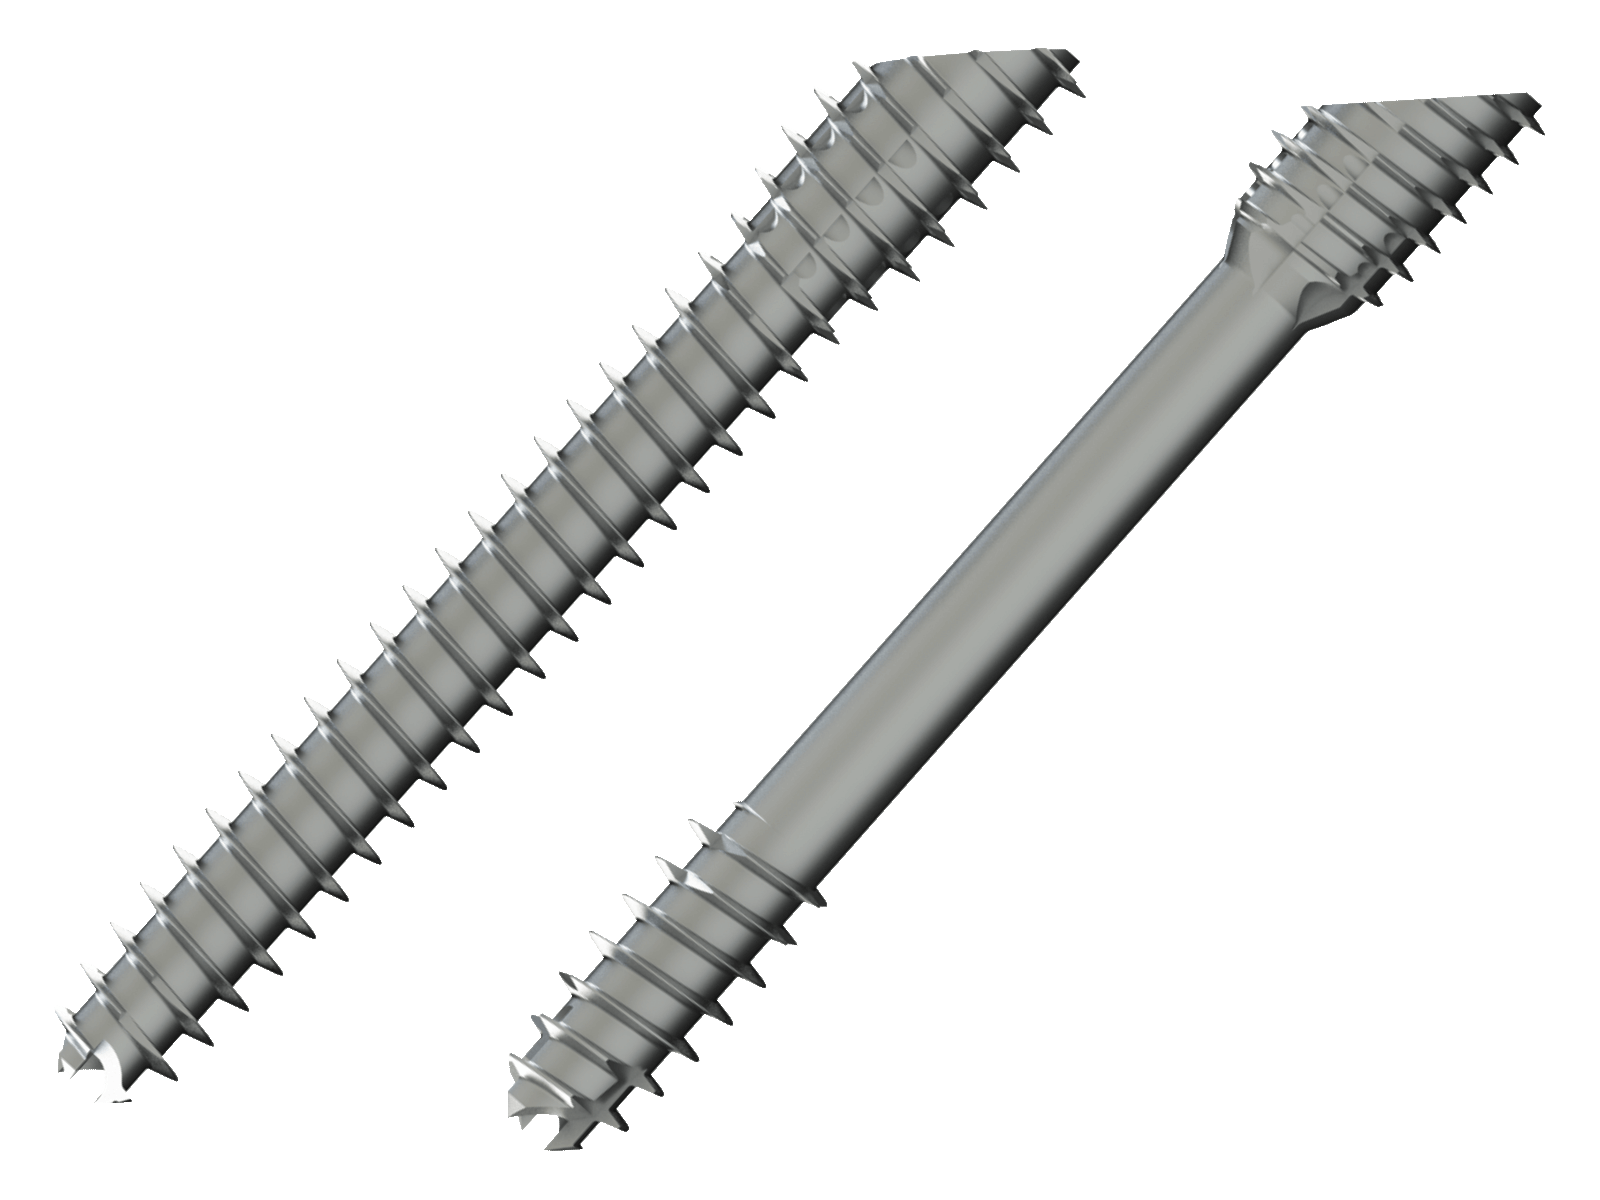

Fixation Devices - Compression Hardware

IBS™-B Beveled Screw System

IBS™-B Beveled Screw System delivers the strength, control, and versatility your MIS workflow demands.